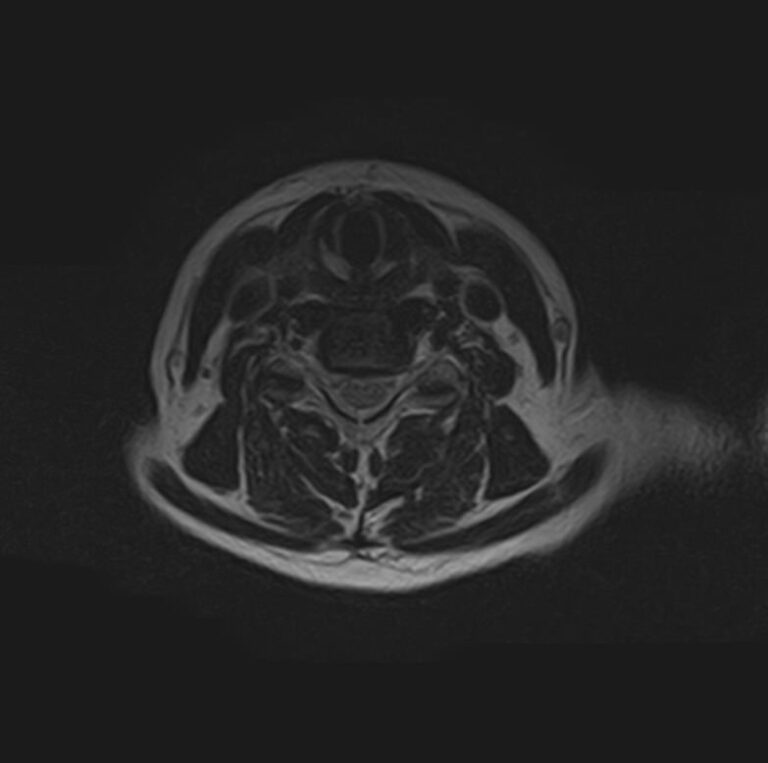

Сканирование проводится на современном высокопольном магнитно-резонансном томографе закрытого типа TOSHIBA VANTAGE TITAN 1,5 Тесла, который делает послойные срезы в разных плоскостях с шагом от 1 мм и на основе полученных данных создает трехмерные изображения превосходного качества. Метод исследования позволяет в мельчайших подробностях визуализировать состояние всех структур головного мозга и шейного отдела позвоночника, что дает возможность выявлять патологические изменения на ранних стадиях и назначать своевременное лечение.